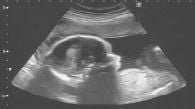

29.abr.2014Nascituro faz jus a indenização por falecimento do paiPara tribunal português, desde a vida intrauterina são percebidas sensações que acompanharão a pessoa vida afora